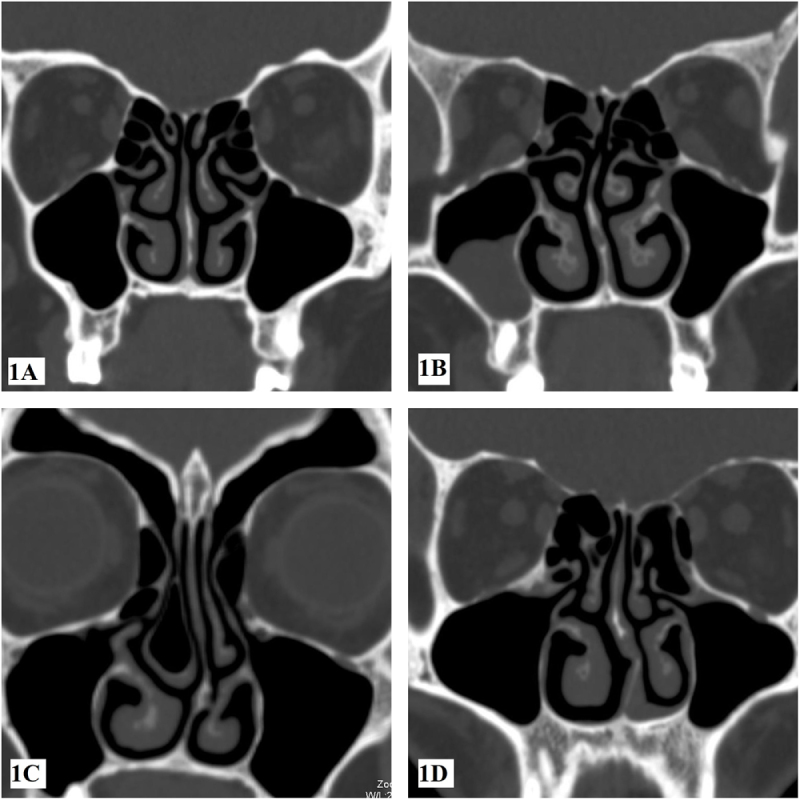

Abstract Image